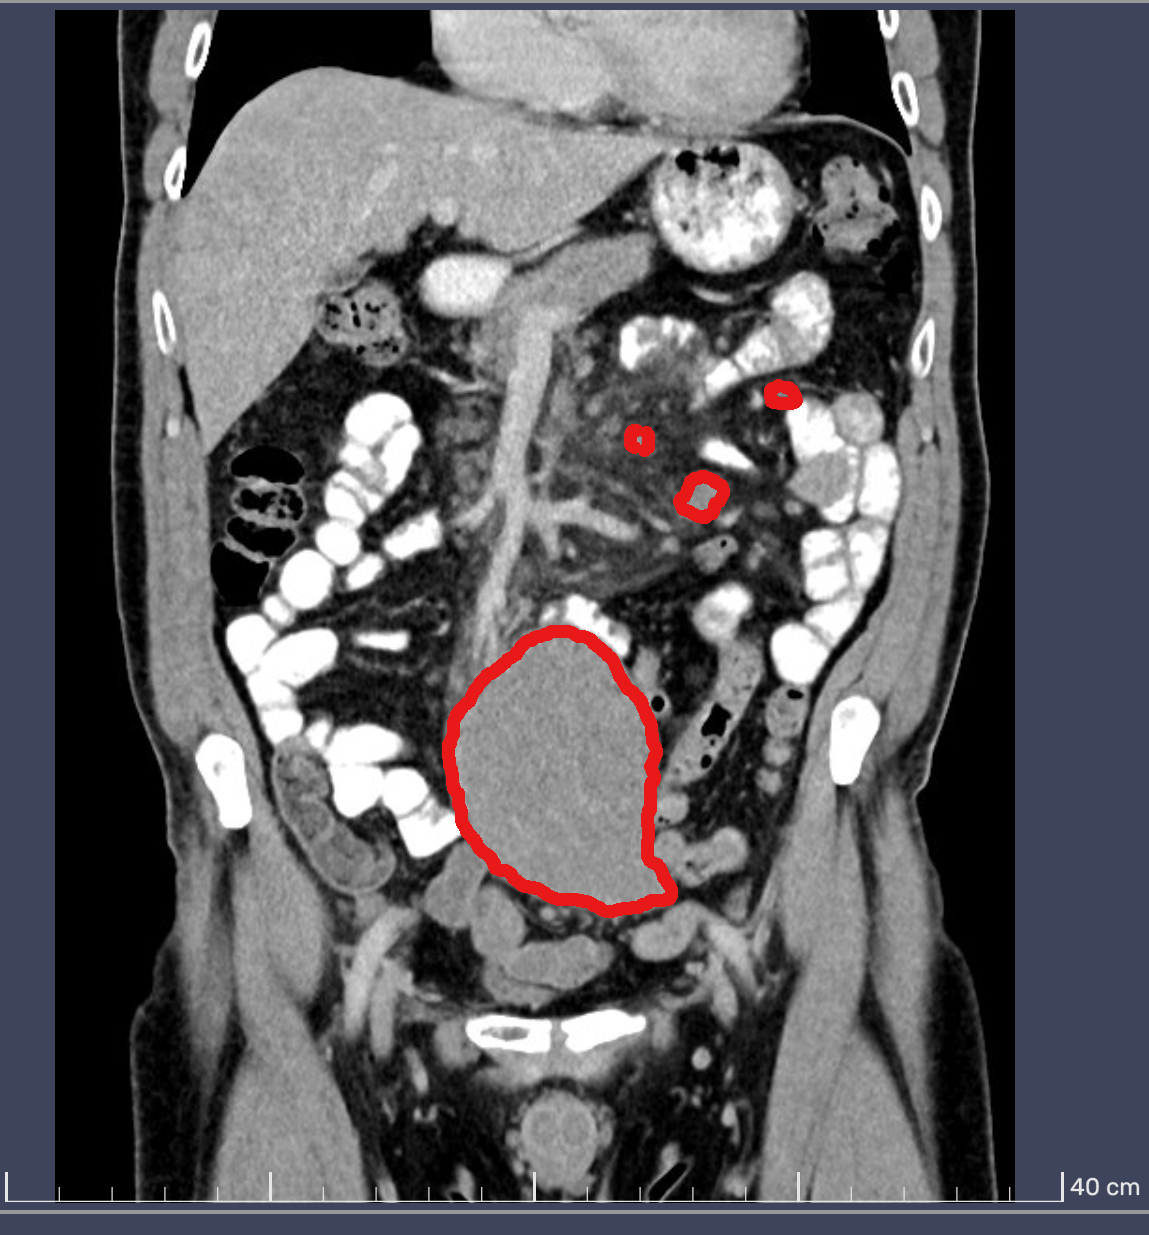

Befund CT

Verdacht Lymphom

Radiologie NURAMED

Die Diagnose und die Bilder von der Computerturmographie schrecken mich nicht ab. Es ist gut, dass durch den Zufallsbefund die Lymphome erkannt wurden.  Meine Frau fragte, den Urologen, ob er noch mal ein Blick auf die Nieren werfen könnte. Schon einige Monate trat